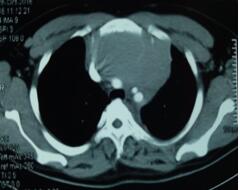

當(dāng)看到病人的CT等外院各項(xiàng)檢查時(shí),我頭皮發(fā)麻,心頭發(fā)怵:巨大的腫塊占據(jù)著整個(gè)縱隔,壓迫心臟,與血管關(guān)系密切,初步考慮侵襲性胸腺瘤、胸腺癌或淋巴瘤等,合并腎功能不全,無(wú)法完整切除,手術(shù)風(fēng)險(xiǎn)大,手術(shù)并不能提高病人長(zhǎng)期生存率,換言之,小伙子等待的是生命的立即終結(jié)。